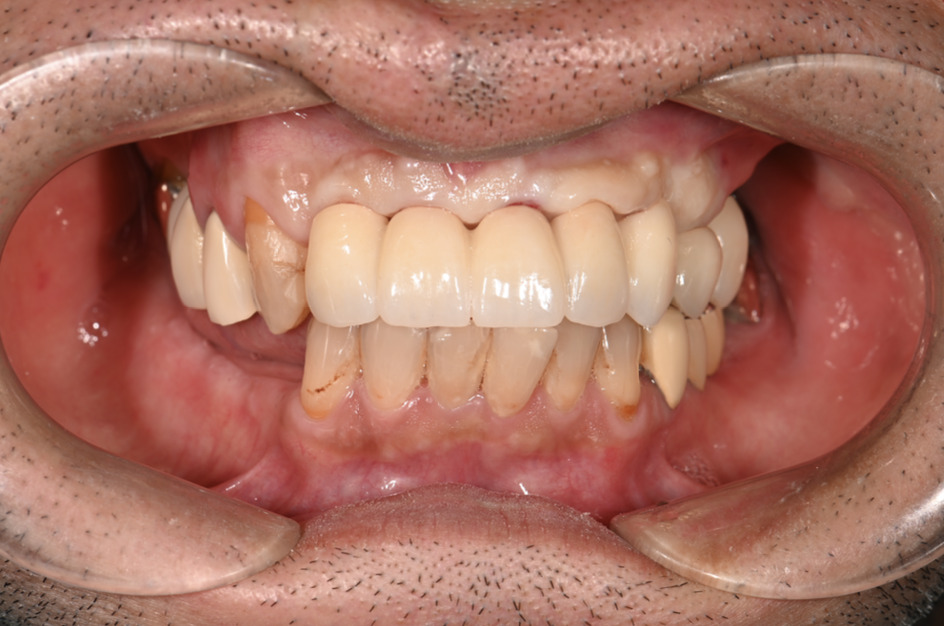

| 主訴 | 歯がグラグラして噛めない |

|---|---|

| 治療内容 | 上顎、下顎に対するインプラント治療 |

| 治療期間 | 1日 |

| 治療費 | 409万2千円 |

| 治療 リスク | 最終的な歯が入るまでは仮歯になります。 |